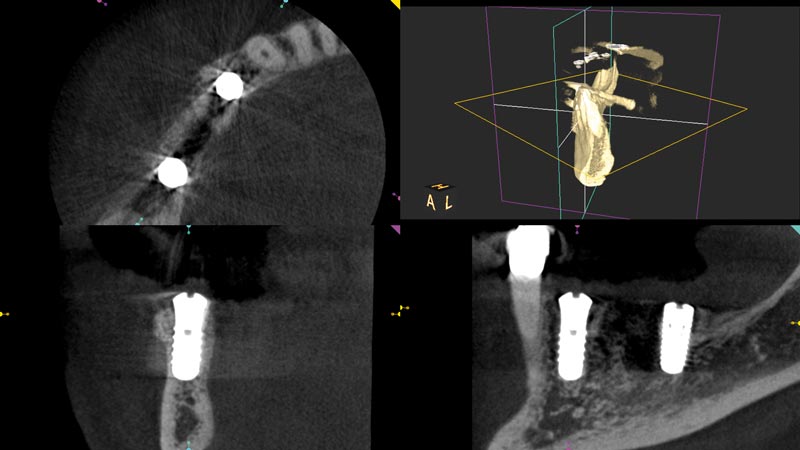

11/14 - CBCT scan post implantation

Block augmentation with maxgraft® in the mandible - PD Dr. Dr. F. Kloss